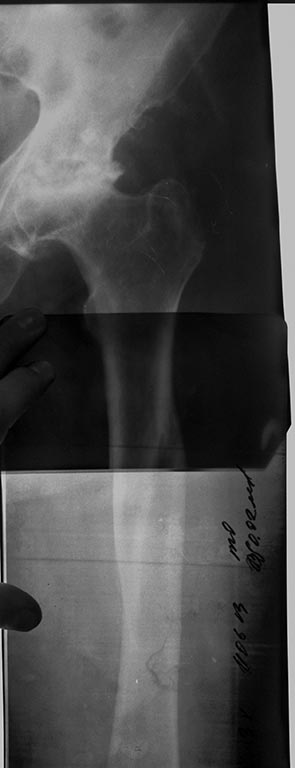

Пациентка Н. 57 лет, поступила в отделение ортопедии с жалобами на боли

в левом тазобедренном суставе. Со слов, считает себя больной около 2-х

лет. Вначале боли были слабые, затем усились и не прошли до настоящего

момента. Консервативно не лечилась. Поступил на плановое оперативное

лечение эндопротезирование левого т/б сустава. А анамнезе в 1980 год –

закрытый перелом бедренной кости в в\3, лечилась консервативно:

скелетное вытяжение, гипсовая иммобилизация.

В данный момент имеем 2 типа ножек - Zimmer Spotorno и DePuy Corail.

Теперь думаем стоит ли лезть с таким арсеналом? Попадем ли в канал,

точно и не расколем ли бедро? Может лучше ФГУЗ и коротокая ножка? Завтра

выложу результаты РКТ.Заранее спасибо! =)